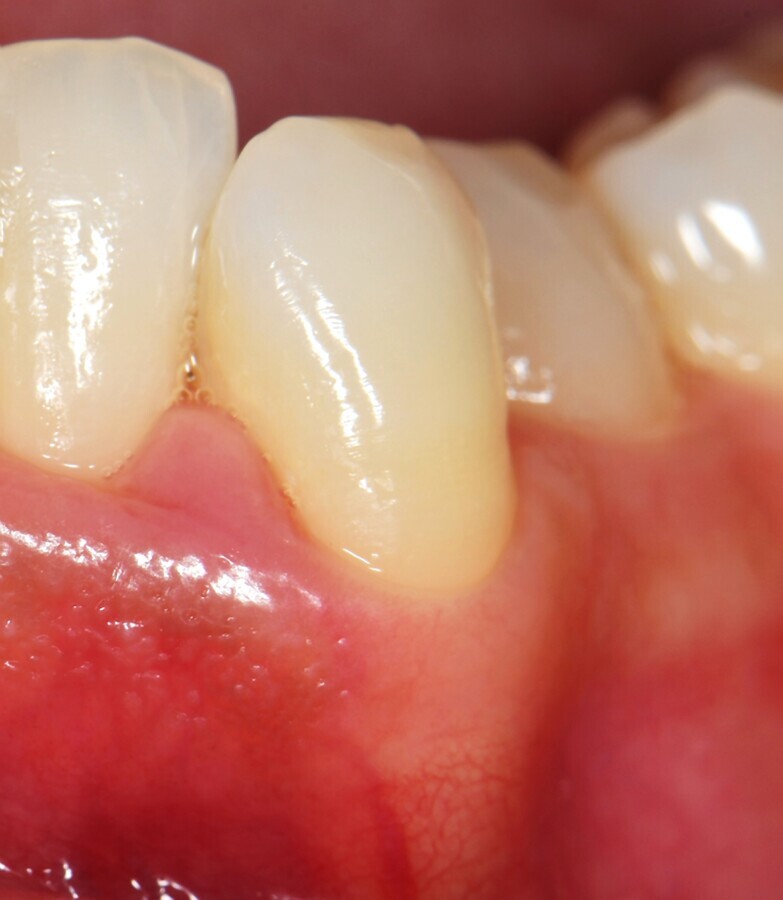

Figura 7. Vista frontal del defecto tratado a los 30 días de seguimiento. Los parámetros periodontales mejoraron: PPD de 3 mm y CAL de 4 mm. El aspecto clínico de los tejidos mejoró significativamente (A). El edema de la fase inicial ha remitido y se observa una depresión en el centro de la papila, lo que indica un estado avanzado de cicatrización (B).